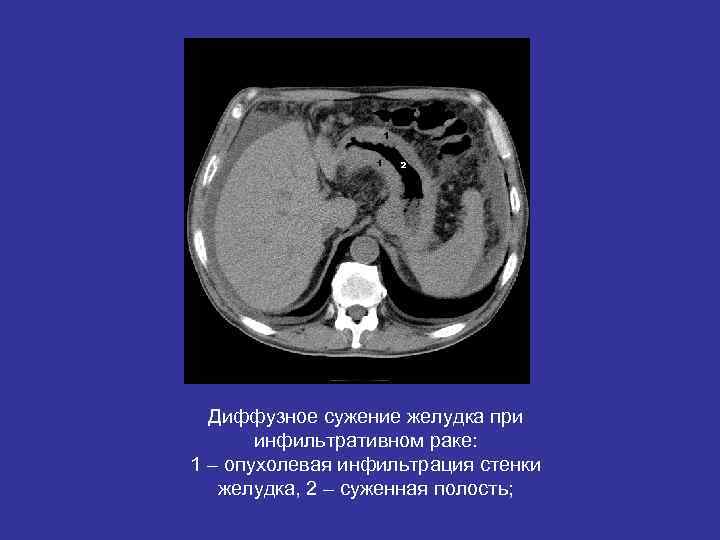

Диффузное сужение желудка при инфильтративном раке: 1 – опухолевая инфильтрация стенки желудка, 2 – суженная полость;